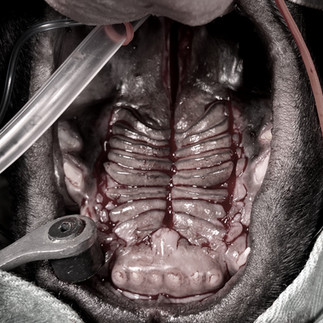

症例:フレンチブルドック、3ヶ月齢、2.6kg、♂

主訴:先天性口蓋裂

治療:口蓋裂の整復(ダブルフラップ法)

硬口蓋から軟口蓋にかけて口蓋裂があります。

まず縫合部の硬口蓋/軟口蓋粘膜を切開して新鮮創に、左右歯列内側の硬口蓋粘膜を大口蓋動脈の損傷に注意して切開後、丁寧に硬口蓋粘膜を骨膜から剥離し、内側へ寄せて口蓋裂を閉鎖しました。

術中は吸引嘴管を用いて出血を吸引除去することで視野の確保と術後の鼻出血を最小限に抑えることができました。

軟口蓋は、鼻腔側と口腔側の二層縫合で閉鎖しました。

縫合部全体として、余計な張力が掛かる感触はなく余裕があり、ポビドンヨードで消毒して終わりました。